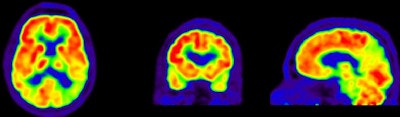

FDG-PET images show a normal brain (top) with normal functions (red) compared with an abnormal brain (bottom) with a diagnosis of Alzheimer's and lack of FDG uptake (yellow and green).In addition, two-year clinical follow-up in a subsample of 39 patients showed that PiB and FDG predicted progression to Alzheimer's disease for patients with mild cognitive impairment, and that the diagnosis of dementia established after PET remained unchanged in 96% of the patients.